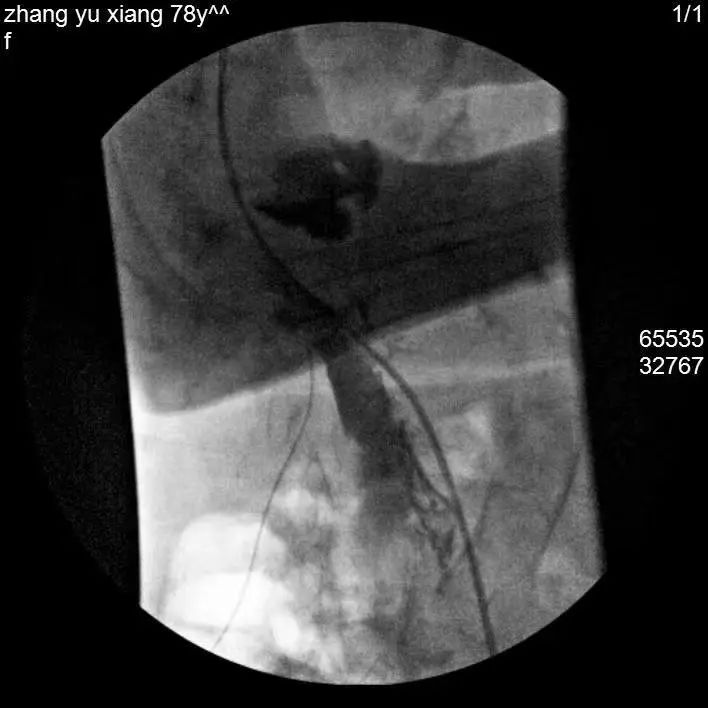

经过细致的检查评估,曹玮主任决定采用目前国际上较为成熟的“脊髓电刺激”疗法来为张阿姨治疗糖尿病足性疼痛,并避免截肢。脊髓电刺激治疗是一种微创疼痛治疗技术,它是在脊髓的硬膜外后间隙插入一根电极,通过电刺激阻断疼痛信号的传导,同时可调控交感神经以改善糖尿病足的末梢血运循环。但是由于张阿姨长期患有类风湿性关节炎,脊柱及四肢严重畸形,无法俯卧位,且椎管多节段狭窄,常规操作无法将电极植入脊椎预定位置,为治疗带来了很大难度。为此,曹玮主任及其团队决定创新采用血管鞘介入技术辅助电极植入,用穿刺针成功引入导丝、导管及血管鞘,通过血管鞘成功建立电极植入通道,之后成功将电极植入至硬膜外脊髓背侧预定的相应刺激区域。在术中测试及术后随访中,张阿姨表示下肢疼痛明显减轻。

经穿刺针置入导丝引导,置入导管及鞘管、引导电极植入